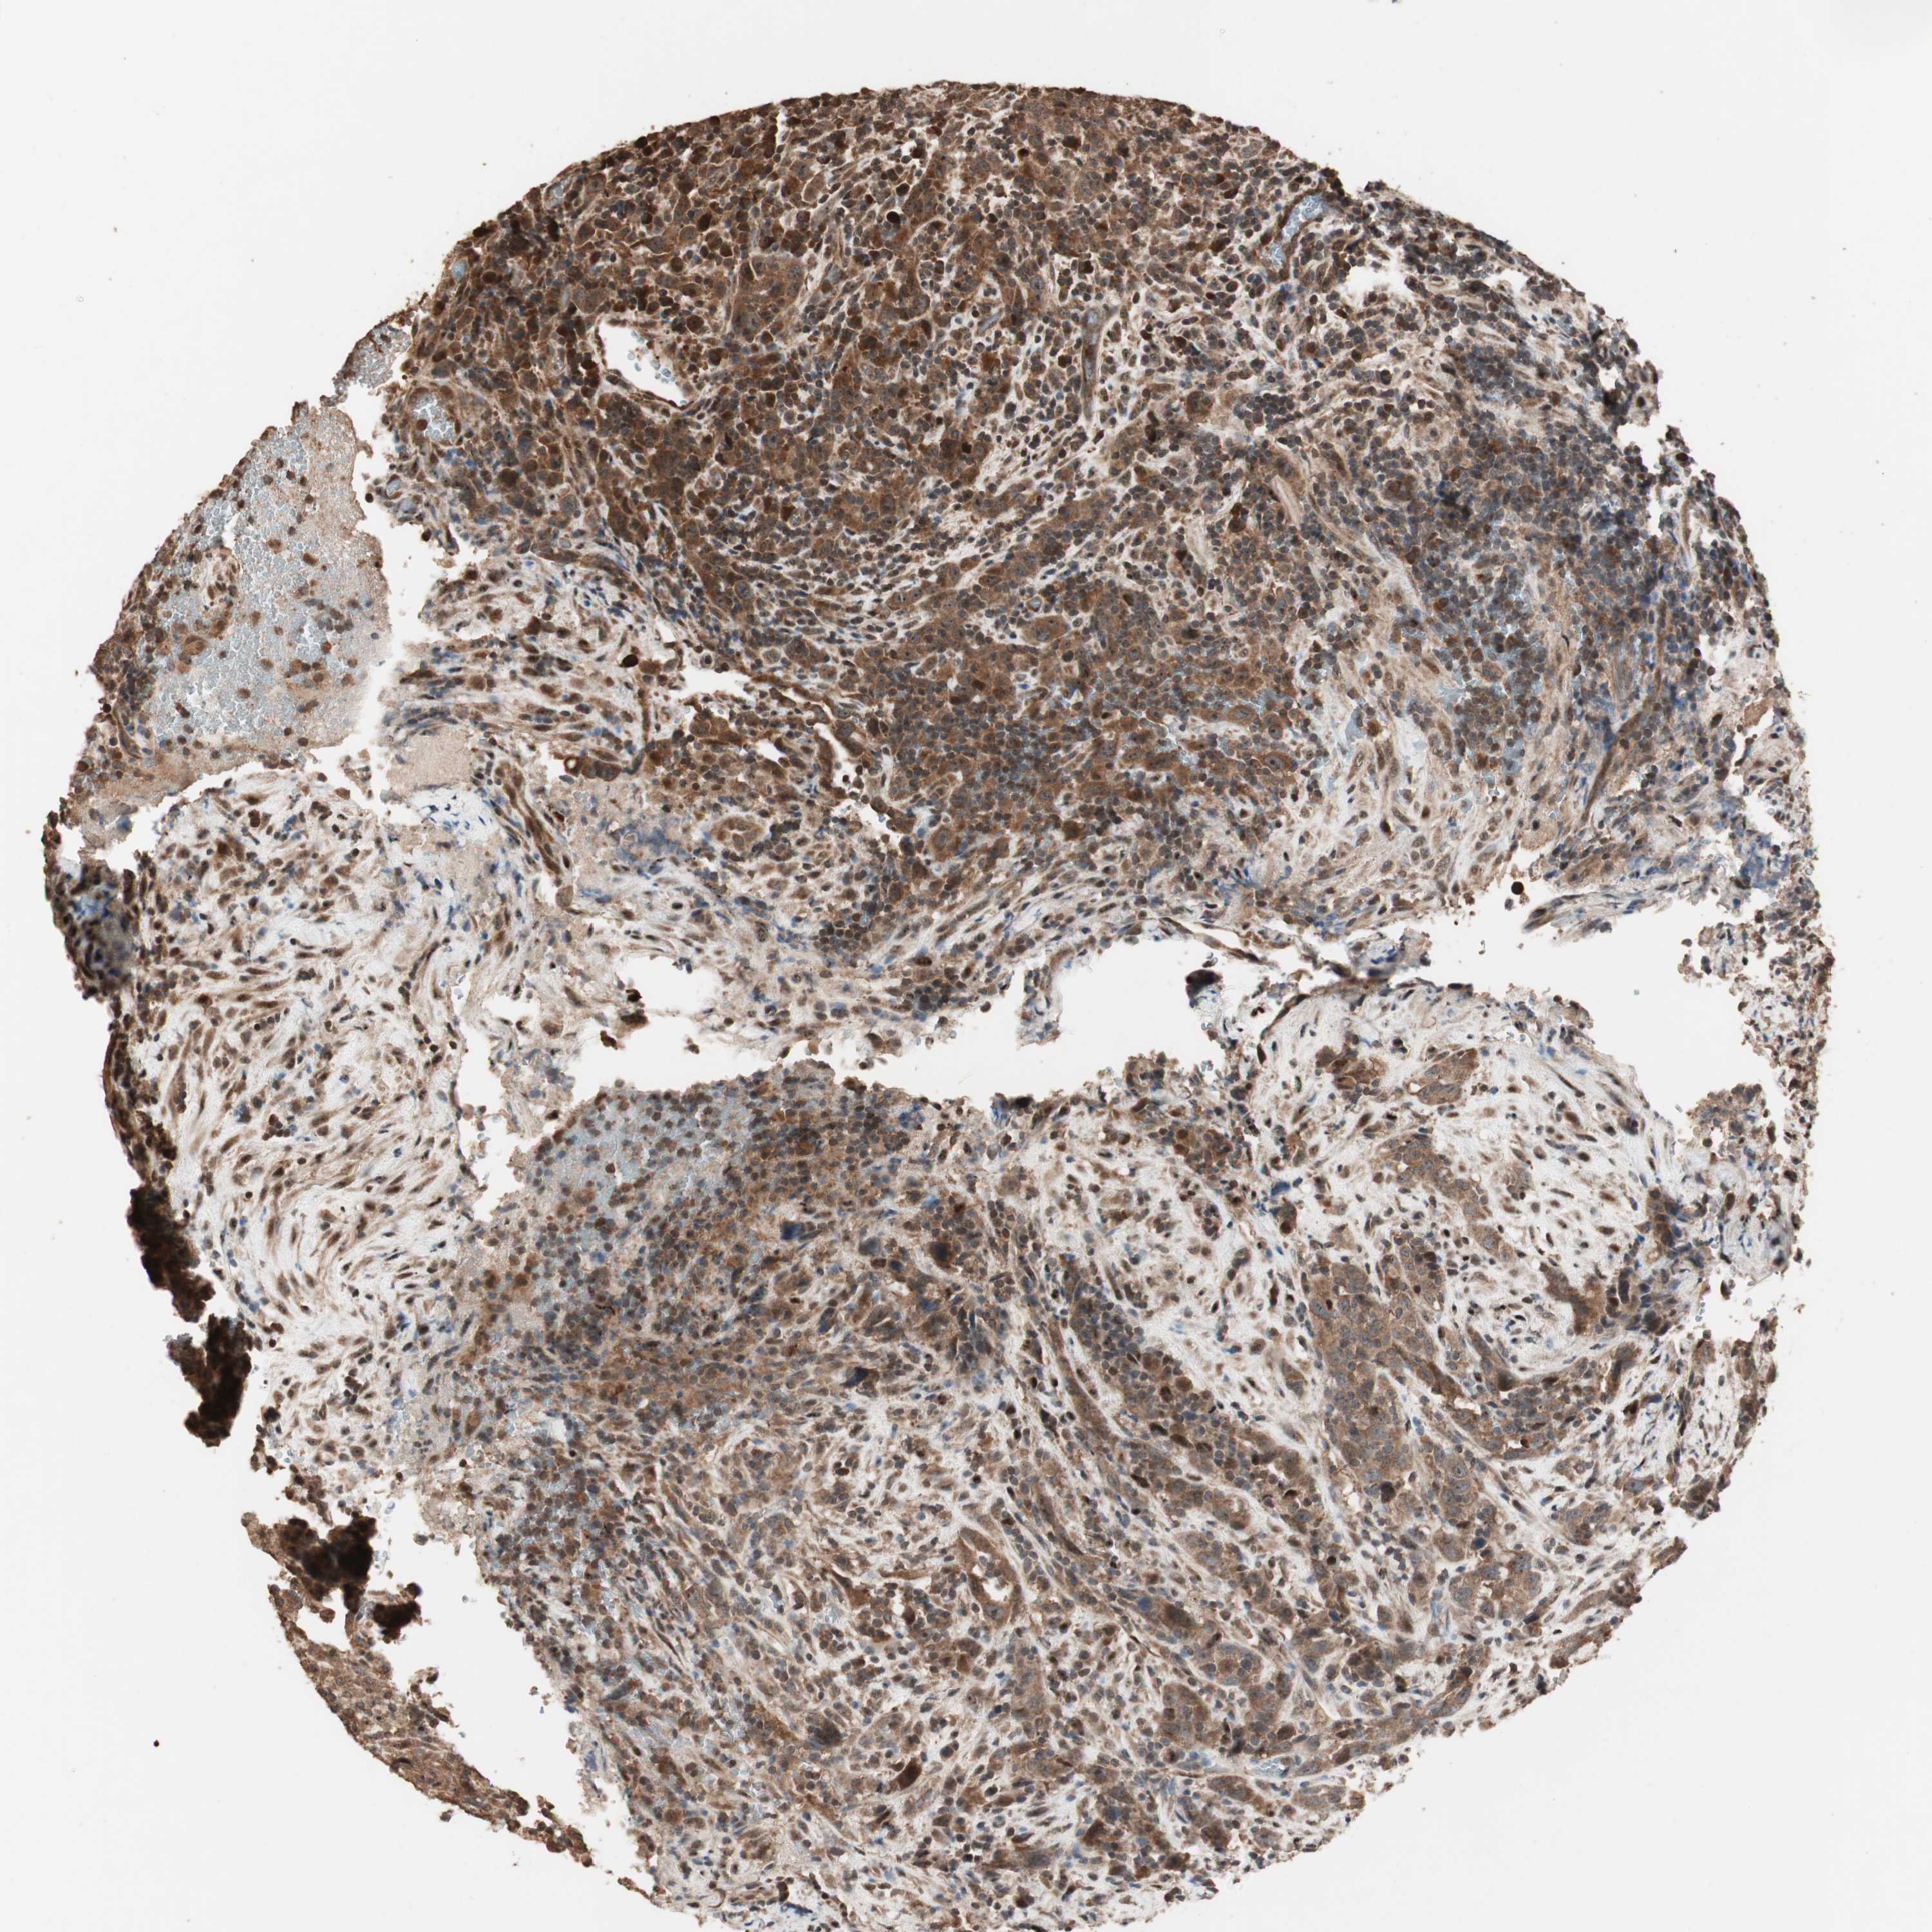

UROTHELIAL CANCER - Protein expressioni

A mouse-over function shows sample information and annotation data. Click on an image to view it in a full screen mode. Samples can be filtered based on level of antibody staining by selecting one or several of the following categories: high, medium, low and not detected. The assay and annotation is described here.

Note that samples used for immunohistochemistry by the Human Protein Atlas do not correspond to samples in the TCGA dataset.

Antibody stainingi

Antibody staining in the annotated cell types in the current human tissue is reported as not detected, low, medium, or high, based on conventional immunohistochemistry profiling in selected tissues. This score is based on the combination of the staining intensity and fraction of stained cells.

Each image is clickable and will lead to virtual microscopy that enables deeper exploration of all samples and also displays staining intensity scores, fraction scores and subcellular localization as well as patient and tissue information for each sample.

Antibody HPA006287

Staining

High

Medium

Low

Not detected

Intensity

Strong

Moderate

Weak

Negative

Quantity

>75%

75%-25%

<25%

None

Location

Nuclear

Cytoplasmic/membranous

Cytoplasmic/membranous,nuclear

Urothelial carcinoma, Low grade

Urothelial carcinoma, High grade